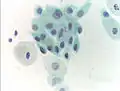

Normal squamous epithelial cells in premenopausal women -

Atrophic squamous cells in postmenopausal women

Normal endocervical cells should be present into the slide, as a proof of a good quality sampling

Pap tests commonly examine epithelial abnormalities, such as metaplasia, dysplasia, or borderline changes, all of which may be indicative of CIN. Nuclei will stain dark blue, squamous cells will stain green and keratinised cells will stain pink/ orange. Koilocytes may be observed where there is some dyskaryosis (of epithelium). The nucleus in koilocytes is typically irregular, indicating possible cause for concern; requiring further confirmatory screens and tests.